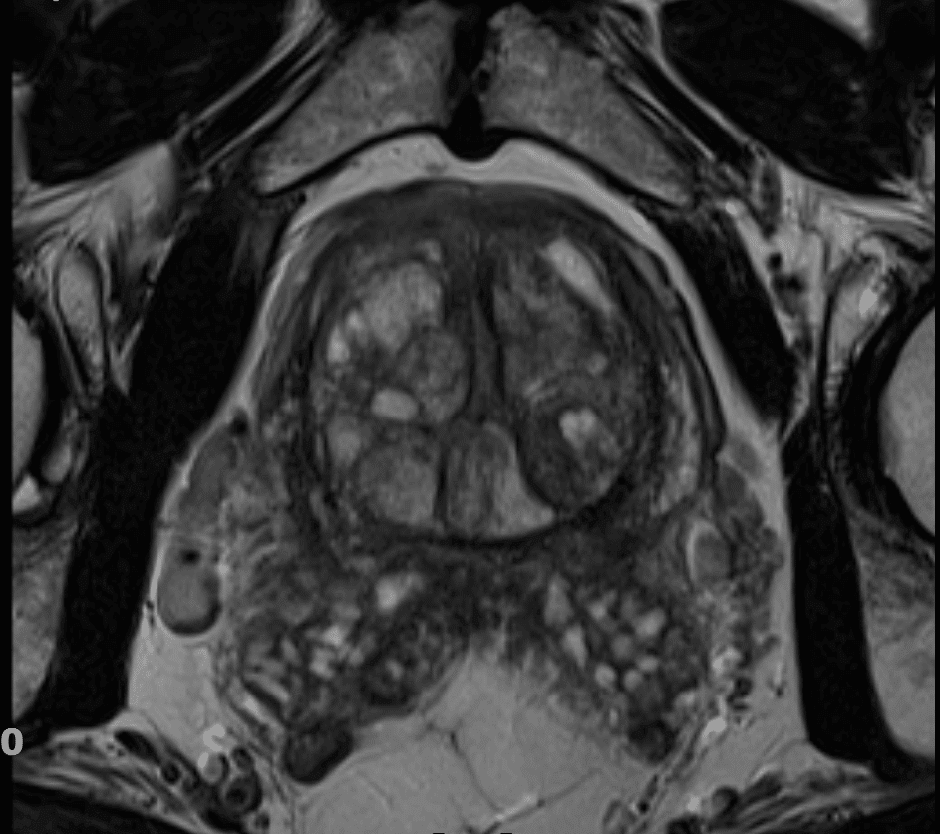

Magnetska rezonanca prostate

Posljednjih nekoliko godina magnetska rezonancija (MR) dovodi do revolucije u dijagnostici raka prostate.

MR bi se u muškaraca s indikacijom za biopsiju prostate praktički trebao učiniti prije same biopsije. Osobito u onih koji su već imali jedan negativan nalaz biopsije. Kako bi MR bio adekvatno izveden članovi EAU i Američkog udruženja radiologa (ACR) preferiraju snimanje prostate na MR uređajima snage 3 Tesle.

Foto: Poliklinika Medikol